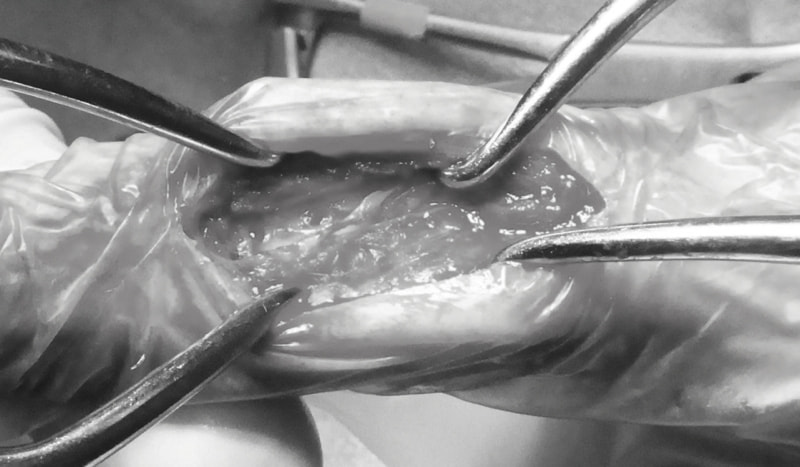

脊髄の減圧、脊柱管の再構築・安定化を目的に、片側椎弓切除術およびMatrixMANDIBLE Plateによる椎体固定を実施しました。

隣接椎体を架橋するようにプレートを設置しました。